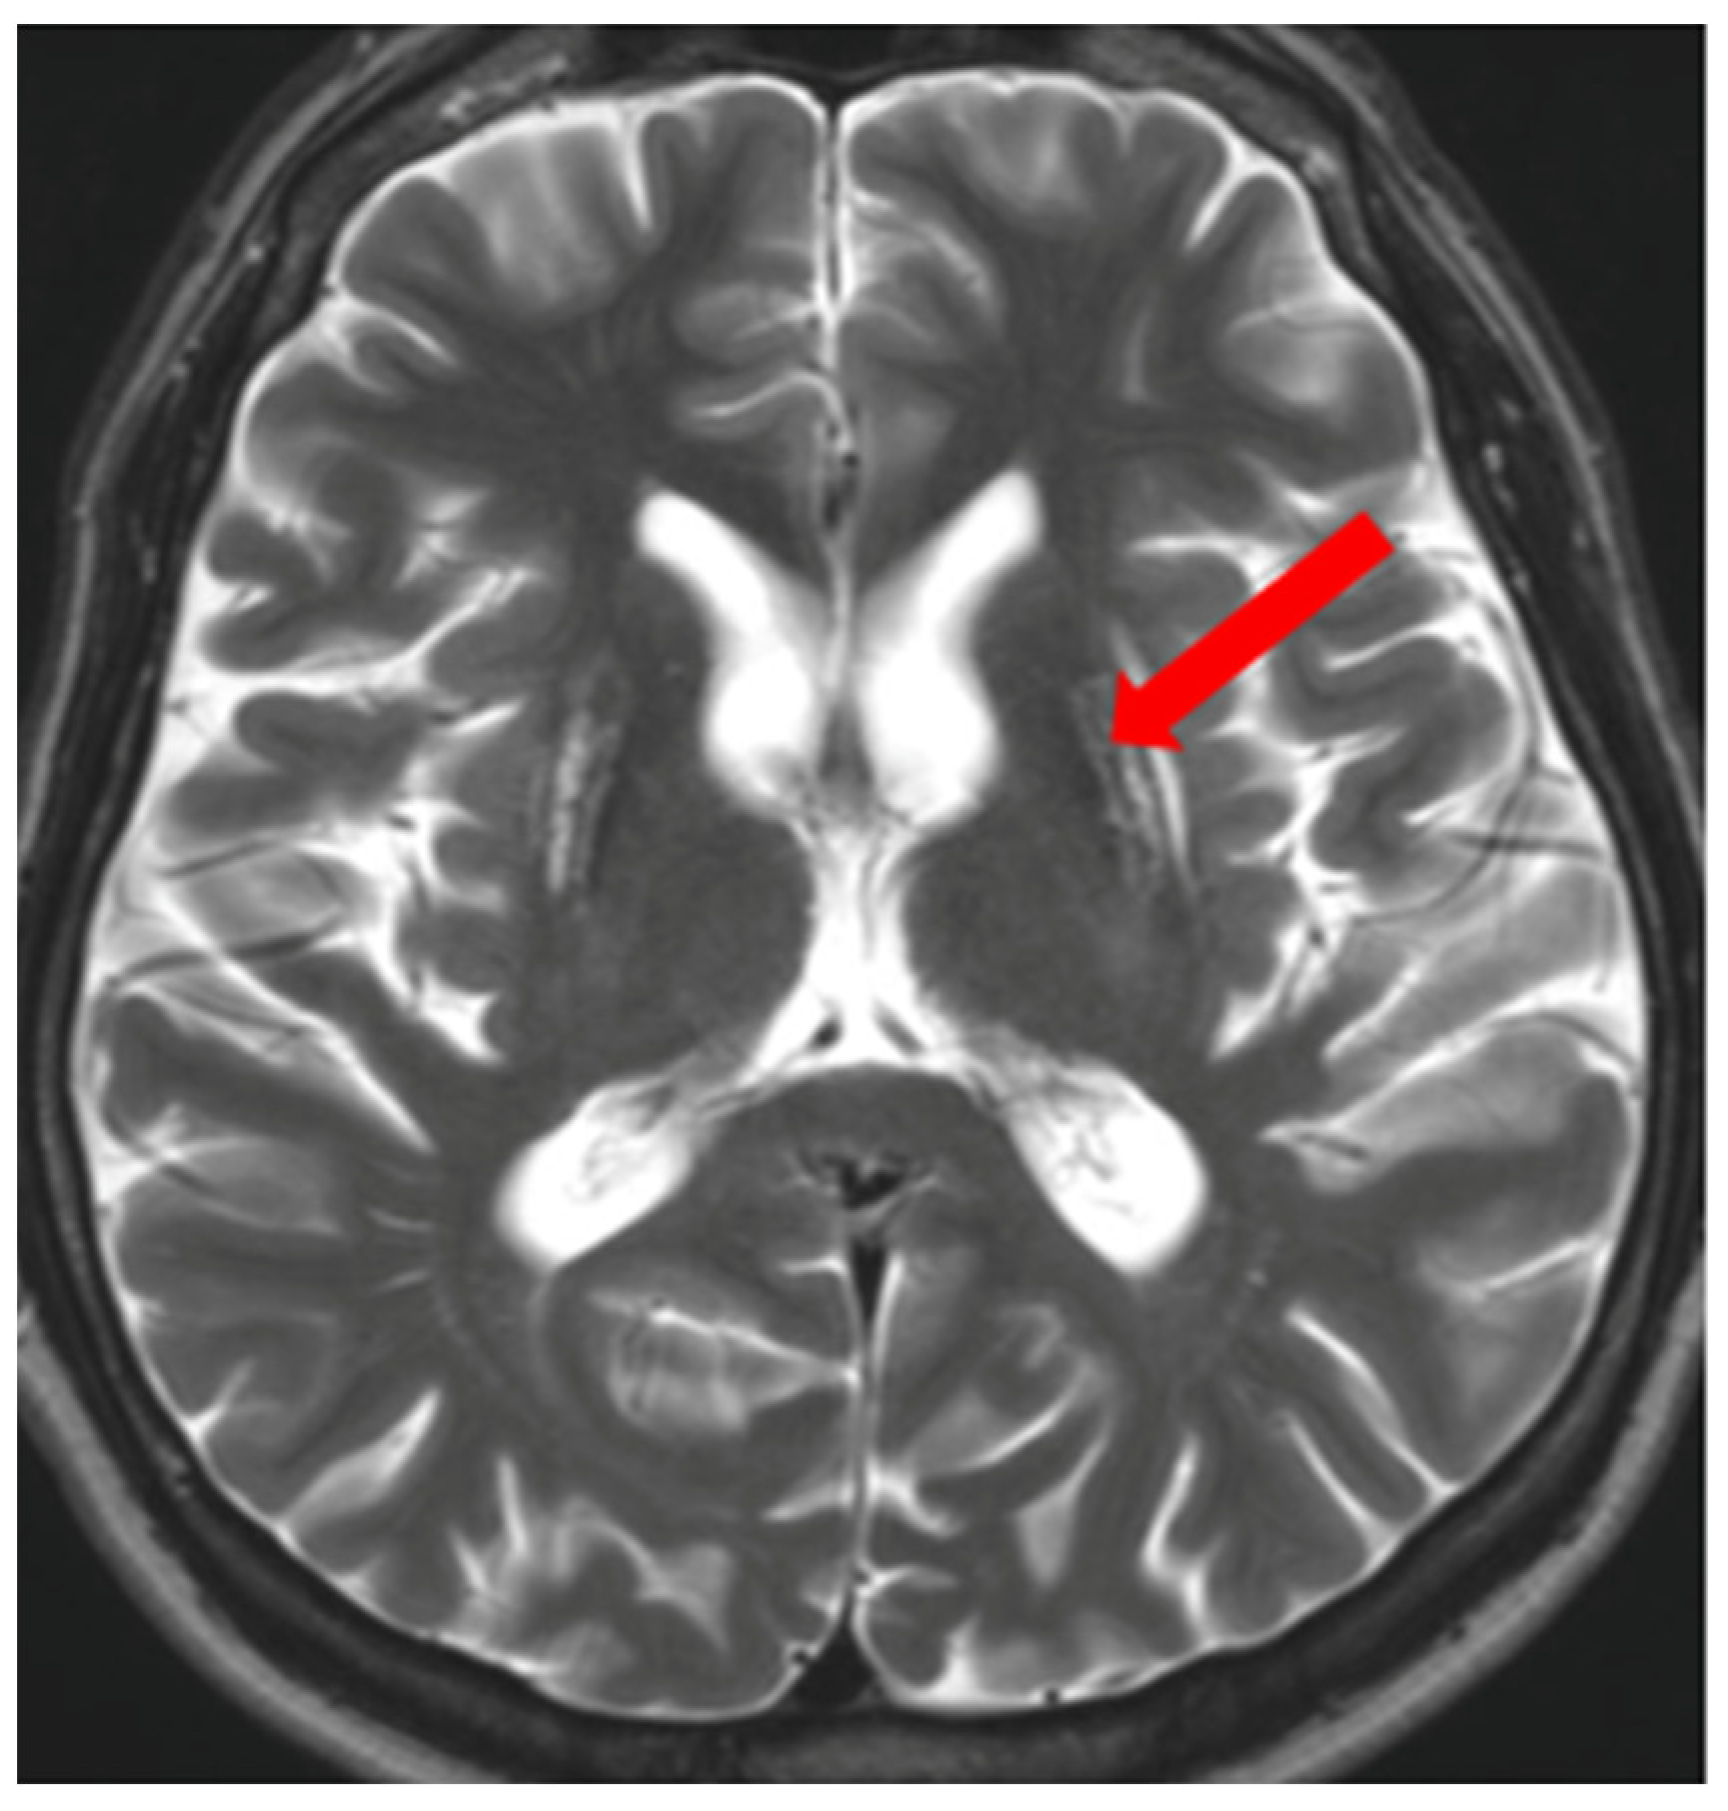

In addition to typical and frequently encountered features among patients with WD, especially in its neurological form, hyper- and hypointense changes in deep brain structures in T2, T2*, FLAIR, and SWI sequences on brain MRI have been noted [10]. Hyperintense foci in the midbrain and pons may sometimes occur in a characteristic pattern with normal brain tissue. Characteristic signs include the ‘face of the giant panda’ in the midbrain and the ‘miniature panda’ sign in the pons, which are considered so-called pathognomonic neuroradiological signs of WD. Besides the aforementioned abnormalities, other pathognomonic signs in WD include the bright claustrum sign, split thalamus (onion sign), and whorl sign [71].

The ‘face of the giant panda’ sign is characterized by an area of increased signal intensity in the midbrain tegmentum and hypointense red nuclei (panda’s eyes), the substantia nigra forming a reticular structure (panda’s ears), and hypointense signal in the superior colliculi (panda’s chin) (Figure 7) [71,72]. The ‘miniature panda’ sign is observed in the pontine tegmentum and consists of hypointense medial longitudinal fasciculi and tegmental tracts (panda’s eyes), hyperintensity of the aqueduct opening into the fourth ventricle (panda’s nose and mouth), with the superior cerebellar peduncles forming the panda’s cheeks (Figure 8) [71,72]. It may appear independently or in conjunction with the ‘face of the giant panda’ sign. In T2 and FLAIR sequences, the presence of a hyperintense internal medullary lamina between the medial and lateral groups of thalamic nuclei has been noted—the split thalamus sign arises from the internal medullary lamina system with significantly increased signal intensity separating the medial and lateral thalamic nuclei with higher signal intensity but lower than the internal lamina (Figure 9) [73]. The whorl sign arises in the putamen due to the coexistence of several concentrically arranged hyperintense bands [15] (Figure 10). The bright claustrum sign arises from the increased signal intensity in the claustrum [74] (Figure 11). In the publication by Su et al., another neuroradiological sign was presented using 7T SWI brain MRI. The hyperintense globus pallidus rim sign was defined as a linear pseudohyperintense signal at the lateral border of the globus pallidus, resulting from the hypointense signal of the globus pallidus and putamen [75].

Figure 9.

The split thalamus sign—increased signal intensity of the internal medullary lamina between the medial and lateral groups of thalamic nuclei (arrow) (own materials of the neurology department).